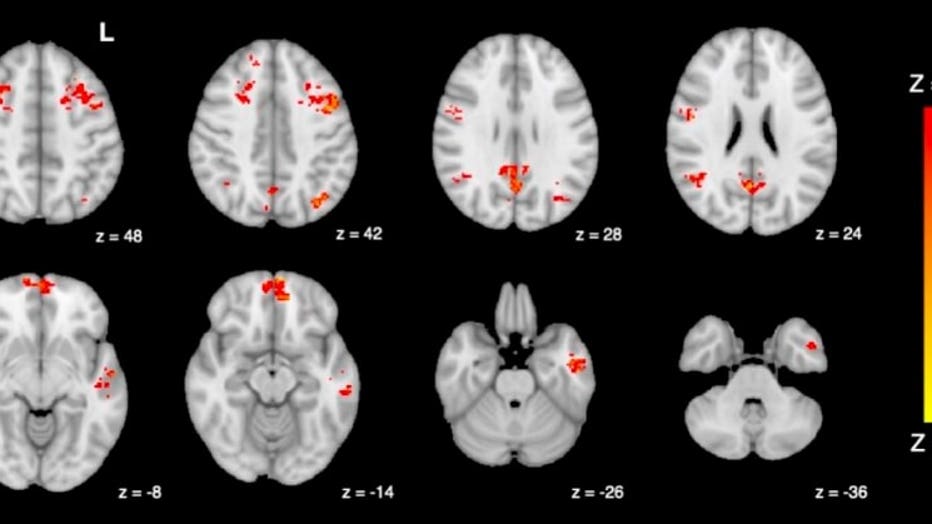

In the study, 25 healthy adults were exposed to either diesel exhaust or filtered air, and functional magnetic resonance imaging (fMRI) was then used to measure their brain activity before and after each exposure.

A fMRI shows decreased functional connectivity in the brain following exposure to traffic pollution. / University of British Columbia

The scans that analyzed the brain's default mode network (DMN) - which includes several connected brain regions that impact one's internal thoughts and memories - showed that people exposed to diesel exhaust have lower DMN activity compared to the air-filtered group.